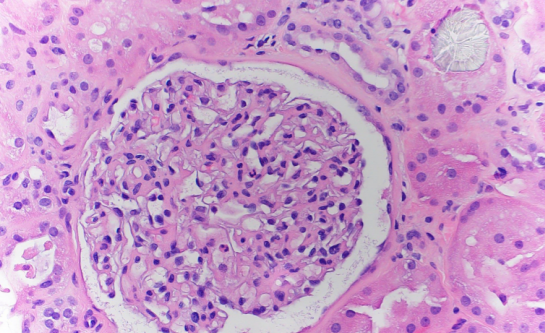

患者的AKI病因尚不清楚,因为只是短暂低血压,没有服用肾毒性药物。怀疑草酸肾病是因为他的24小时尿草酸浓度为40mg(参考范围16-49ml/d),血清草酸浓度为22.5mmol/L(参考范围≤1.9). 在第4天进行肾活检以确定其AKI的原因。组织学检查显示轻度急性肾小管坏死和微小的间质纤维化。还显示肾小管内广泛的草酸钙晶体沉积,在偏振光下观察时具有特征性的明亮双折射(图1和图2)。患者在入院前否认有任何高草酸饮食史、减肥手术史、炎症性肠病史或任何药物使用史。因此,肾活检结果证实了继发性草酸肾病的诊断,继发性草酸肾病归因于服用羟钴胺。在第5天,患者从连续性肾脏替代治疗过渡到间歇性血液透析。配合低草酸饮食、口服醋酸钙和吡哆醇,每天5 mg/kg。随着时间的推移,患者的排尿量有所改善,但在出院时仍依赖透析。患者最终从AKI中康复,血液透析在出院1个月后停止。

图1